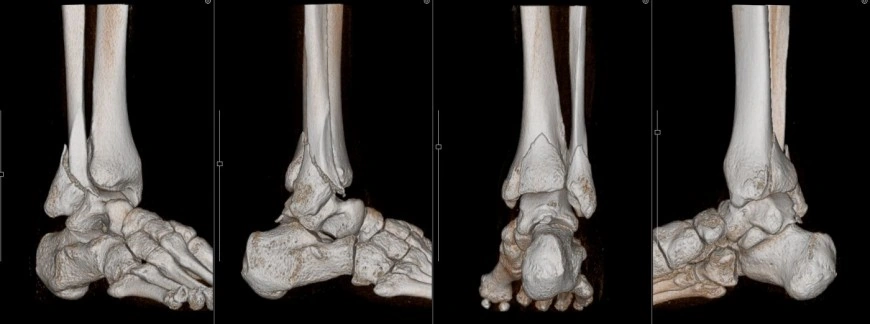

右足関節骨折 MPR